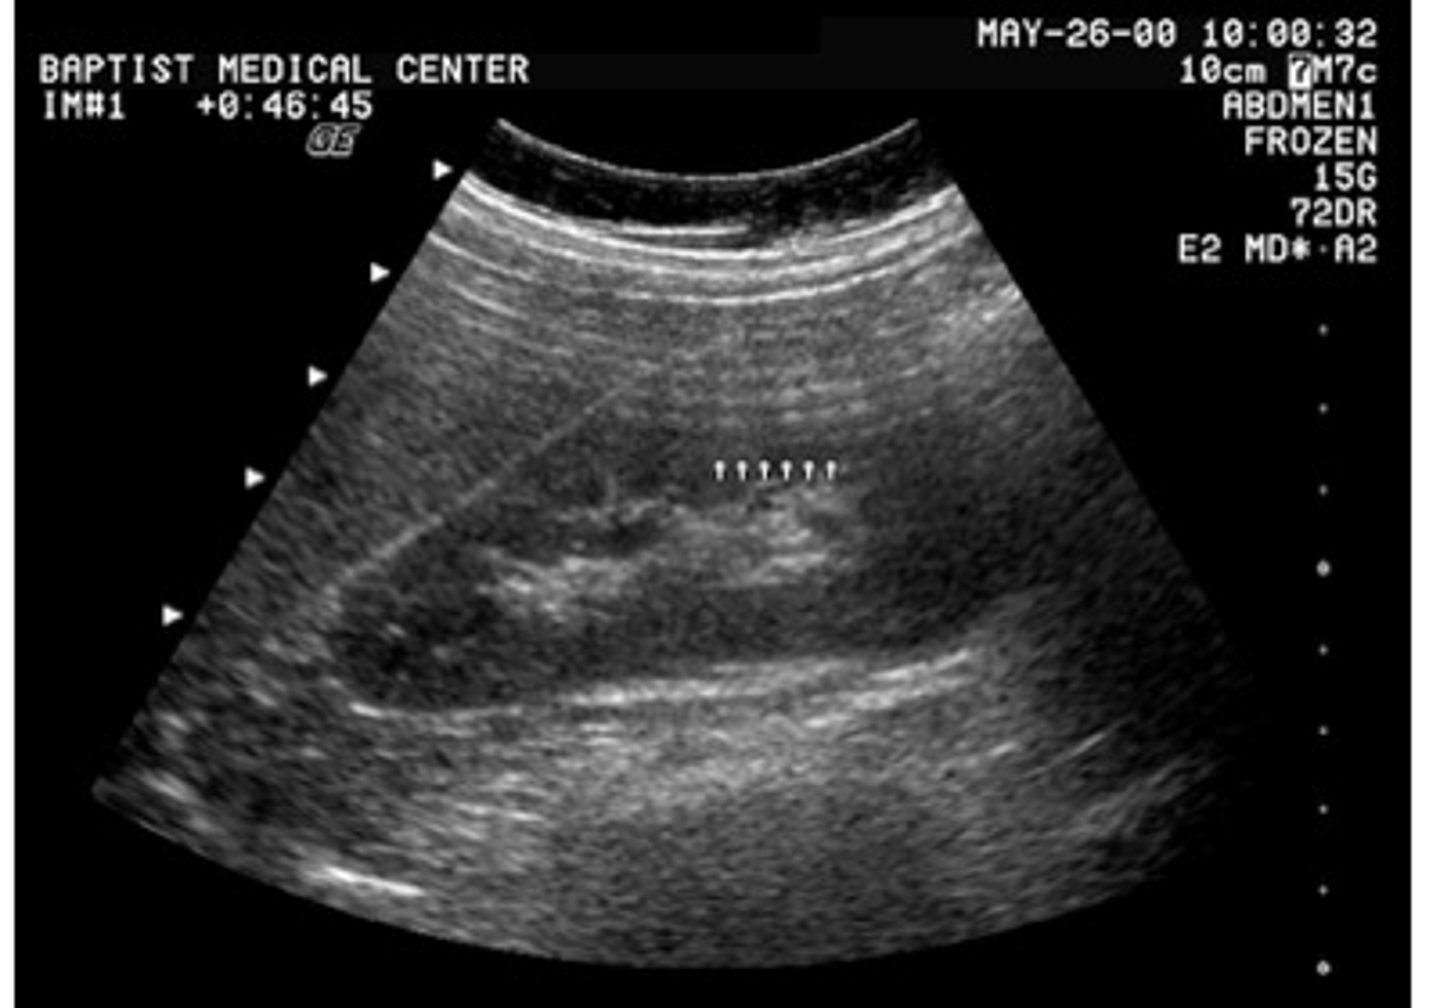

What is the source of the echoes depicted in the image of the kidney?

reverberation

<p>reverberation</p>